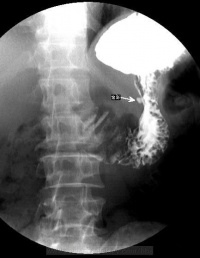

• X线钡餐检查:溃疡的X线征象有直接和间接两种:龛影是直接征象,对溃疡诊断有确诊价值。良性溃疡凸出于胃、十二指肠钡剂轮廓之外,在其周围常见一光滑环提,其外围辐射状粘膜皱襞。间接征象包括局部压痛、胃大弯痉挛性切痕、十二指肠球部激惹和球部畸形等,间接征象仅提示有溃疡。

溃疡-透视

• 胃镜检查:对消化性溃疡可作出准确诊断及良性恶性溃疡的鉴别诊断。胃镜检查不仅可对胃十二指肠粘膜直接观察、摄影,还可在直视下取活检作病理和幽门螺旋杆菌(Hp)检测。它对消化性溃疡的诊断和良、恶性溃疡鉴别诊断的准备性高于X线钡餐检查。在溃疡太小或太表浅,钡餐检查难以发现;钡餐检查发现的十二指肠球部畸形可有多种解释难以确诊;活动性上消化道出血是钡餐检查的禁忌证,内镜检查可确定其来源和性质。钡餐检查或内镜下看似良性的胃溃疡中,大约5%实际是恶性的,反之少部分看似恶性的溃疡,事实证明是良性的,不作活检难以鉴别。此外,内镜检查还可发现伴随溃疡的胃炎和十二指肠炎。内镜下消化性溃疡多呈圆形或椭圆形,偶也呈线状,边缘光整,底部充满灰黄色或白色渗出物,周围粘膜可有充血、水肿,有时见皱襞向溃疡集中。